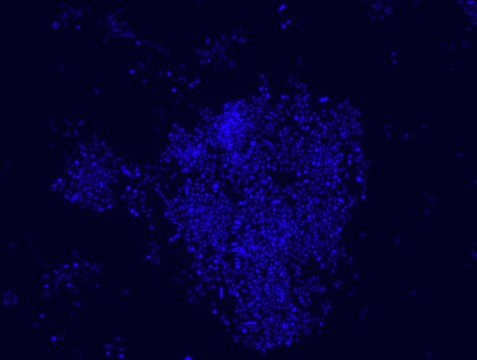

Akkermansia muciniphila probe specifically recognizes Akkermansia muciniphila cells.

FISH technique was successfully used to identify A.muciniphila with the probe in various samples such as pure culture (as described in the figure legends and18), fecal samples 19-21, gut lumen content 22, appendix samples 23, cecum content and tissue24,25 and colon tissue26. The probe can also be used for FISH coupled with flow cytometry (FCM-FISH)19,20,21 and FISH combined with Raman microspectroscopy 24.